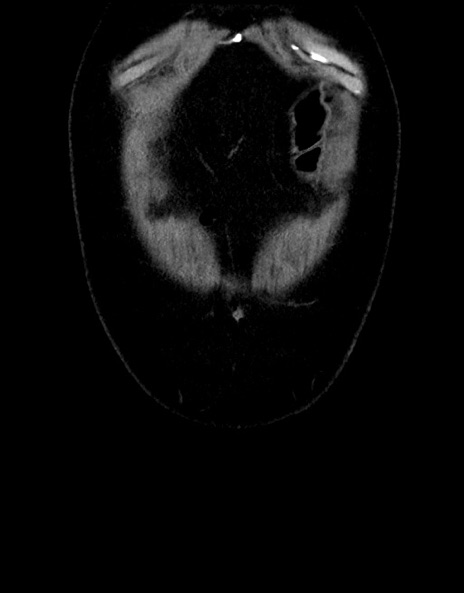

横断像